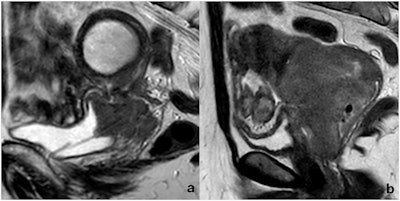

Two cases of MRI-defined bladder wall invasion on sagittal FSE T2-weighted images. (a) A complete loss of neoplasm-bladder cleavage plan, a massive bladder wall thickening with intermediate signal intensity, as well as endoluminal tumor growth, is appreciable; a DJ catheter was placed because of hydronephrosis. (b) An incomplete loss of neoplasm-bladder cleavage plan and a discrete bladder wall thickening with intermediate signal intensity is appreciable, but no endoluminal tumor growth can be observed. The first case was positive at cystoscopy, whereas the second one was negative. Both patients underwent local tumor recurrence (13 and 19 months after chemoradiation, respectively), and both died (25 and 36 months after initial diagnosis, respectively).Bonatti et al; European Radiology